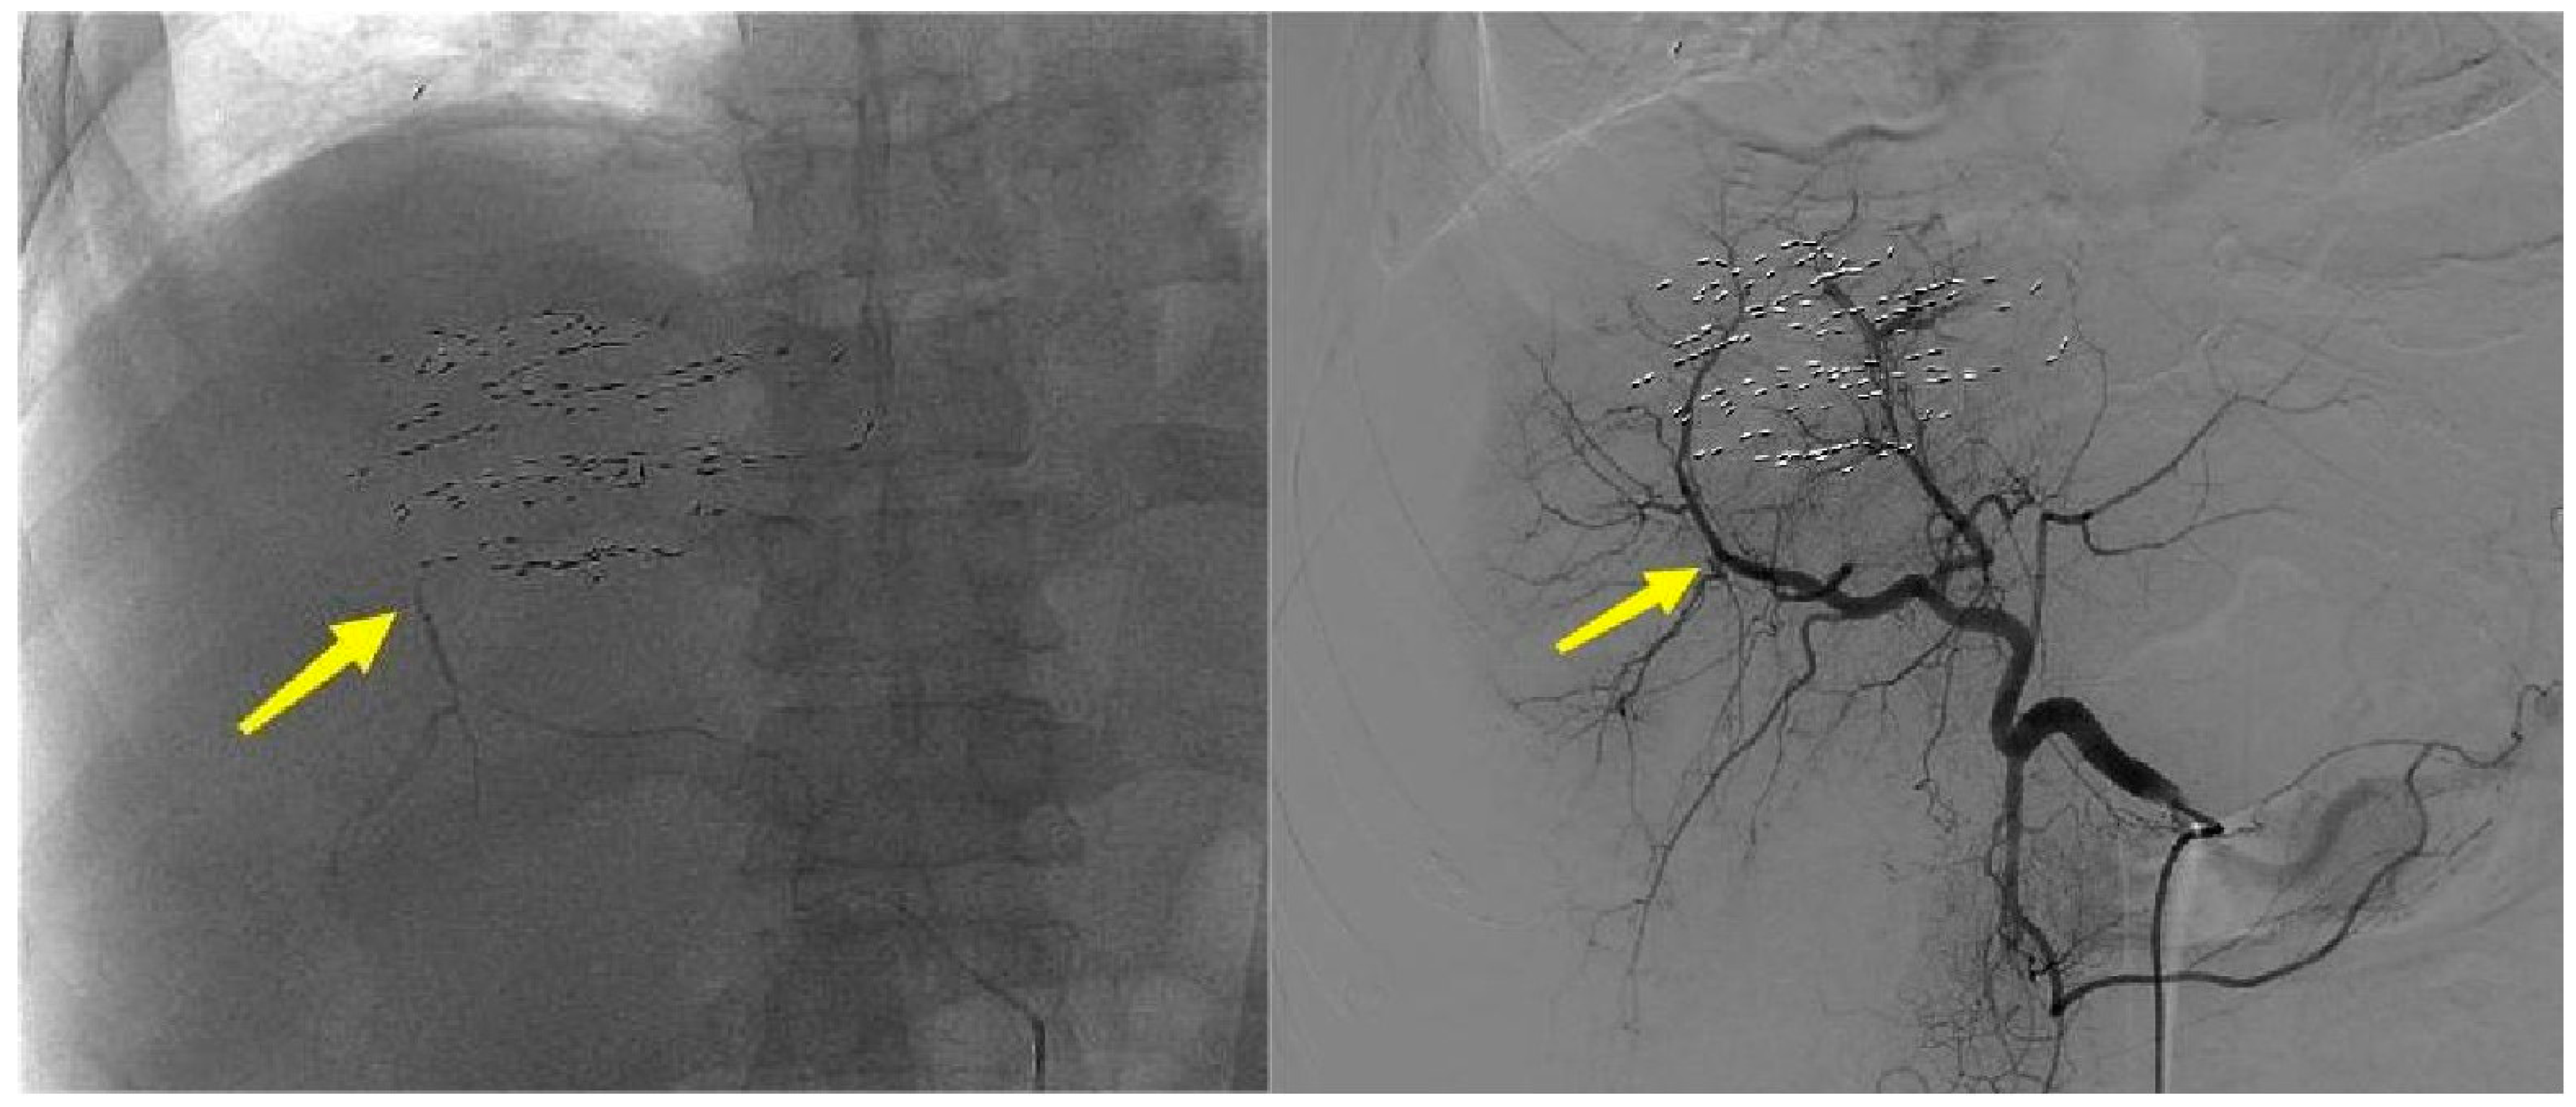

3.1. Imaging Features